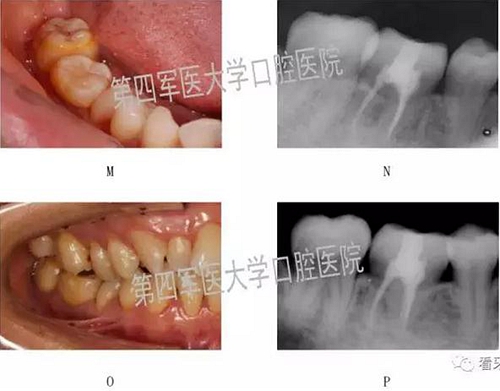

二,牙槽內移植

1,阻生牙牽出再值